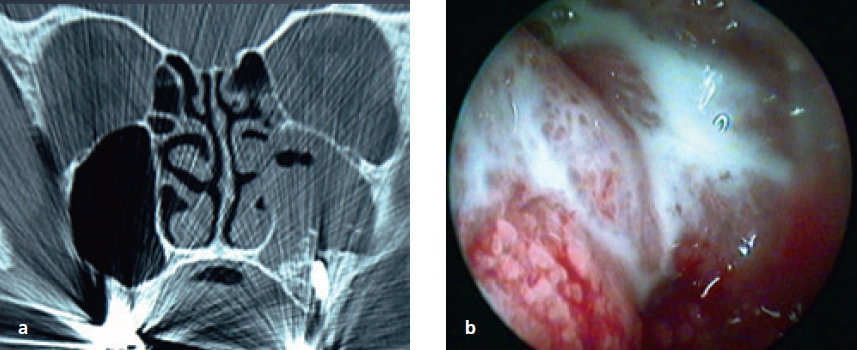

Von dieser Form der Pizerkrankung ist die allergische Pilzsinusitis (AFS, allergic fungal sinusitis) abzugrenzen [16]. Diese immunologische Erkrankung geht mit einer generalisierten NNH-Entzündung (Pansinusitis), Asthma und Polyposis einher (Abb. 12).